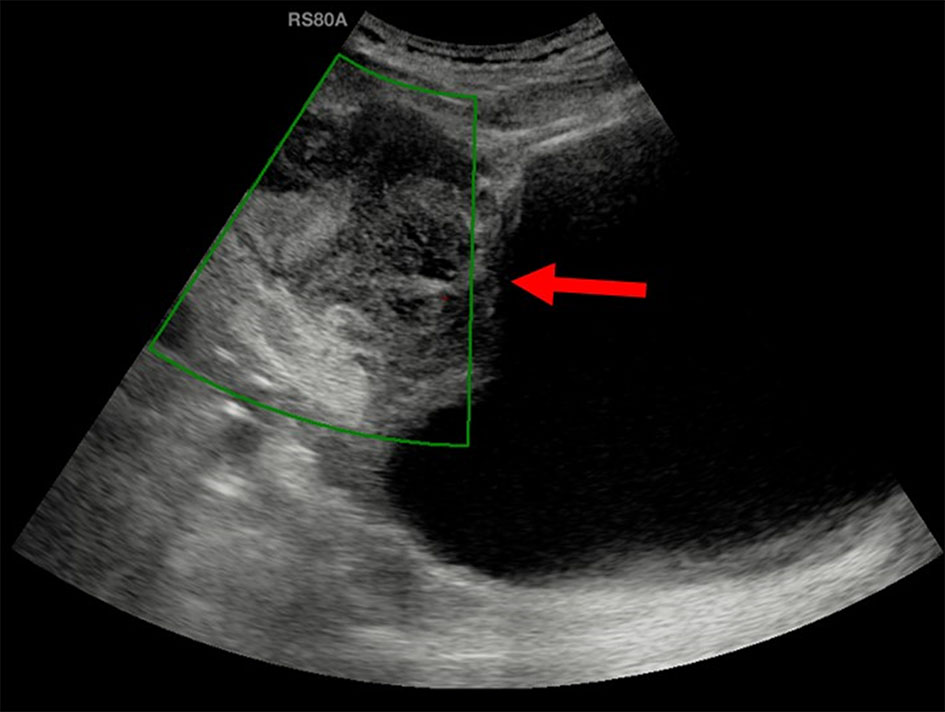

Ultrasound of the abdomen showed moderate sized, ill-defined, heterogeneously hypoechoic mass in the midline lower abdomen. The mass was predominantly extending exophytically antero-superior to the dome of bladder with minimal indentation into the bladder wall. The mass was seen adherent to the dome of the bladder with adjoining moderate wall thickening. On color Doppler, no significant vascularity was noted (Fig. 1). No significant lymph nodes were detected. Rest of the urinary bladder wall was unremarkable. No other significant abnormality was detected in the abdomen. Urachal lesion with possibility of carcinoma was given and contrast-enhanced CT (CECT) of abdomen and pelvis was suggested.

![]() Click for large image | Figure 1. Ultrasound showed a moderate sized, ill-defined, heterogeneously hypoechoic mass (arrow) predominantly extending exophytically antero-superior to the dome of bladder with minimal indentation into the bladder wall. On color Doppler, no significant vascularity was noted. |